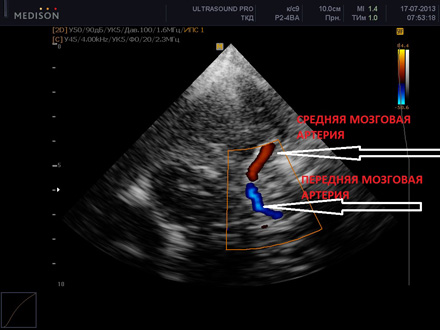

Ультразвуковая допплерография (цветное картрирование) — неинвазивный метод диагностики. Стандартная процедура дает информацию только о проходимости сосудов, для получения прочих данных используют дуплексное или триплексное сканирование. В современных клиниках эти методы иногда совмещают, однако при этом повышается стоимость исследования.

Так как проводится УЗДГ сосудов головного мозга, исследование возможно только через наиболее тонкие участки черепа: глазницу, затылочную и височную кости. Для этого датчики устанавливаются на закрытый глаз, за ушной раковиной и над ней. После фиксации данных пациента усаживают и обследуют затылочную область.

Допплерография (УЗДГ) сосудов головного мозга и шеи позволяет быстро выявлять нарушения в кровотоке, оценить проходимость экстракраниальных сосудов и тех, что находятся в тканях головного мозга. Подробнее о том, как проходит исследование и цены на УЗИ, Вы можете узнать, перейдя по ссылке.